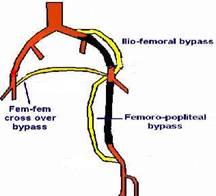

A. 周邊動脈繞道手術: 為改善周邊動脈血流供應,以減少組織壞死情形。可使用達克龍(Dacron)或鐵弗龍(Teflon)人工血管或病人自體的大隱靜脈作為血管繞道之材料。 根據患者病情及需要選擇切口位置,並根據血管阻塞的部位而給予適當的繞道手術。由於可能需要獲取肢體上的靜脈以提供繞道血管,所以有些病人需要其他切口。